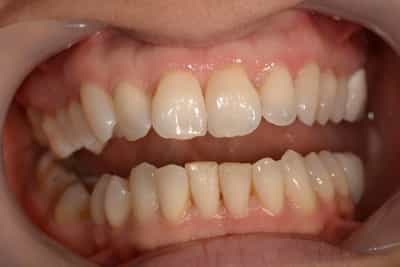

L’éclaircissement dentaire est une technique consistant à rendre aux dents une couleur plus harmonieuse, plus en adéquation avec l’image que le patient veut donner de lui. Le blanc des yeux est une référence. A l’échelle du visage, la blancheur de la sclérotique de l’oeil (blanc des yeux) fait ressortir la couleur jaune des dents. Pour une meilleure harmonie, il faut aligner ces deux couleurs. Si les dents sont moins lumineuses, l’éclaircissement va améliorer l’apparence. Après éclaircissement, cette différence s’atténuera et donnera une harmonie du visage.

Souvent, à partir d’un certain âge, les dents changent de couleurs. Ces changements peuvent être dûs à des colorations extrinsèques. Dans ces cas, un simple nettoyage-polissage peut suffire à y remédier.

Dans d’autres cas, il s’agit d’une usure de l’émail. L’émail est responsable de la luminosité de la dent, et son usure a tendance à révéler la couleur de la dentine sous-jacente. Elle peut être marron, jaune, grise, orange… L’éclaircissement agit sur les colorations intrinsèques et extrinsèques, en surface et en profondeur.